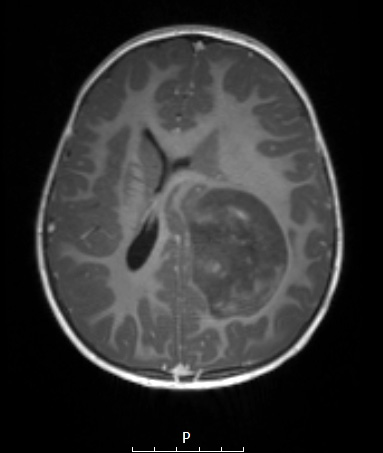

8A2 ETMR (Case 8) T1W - Copy

The mass is hypointense with contrast in this T1-weighted image.